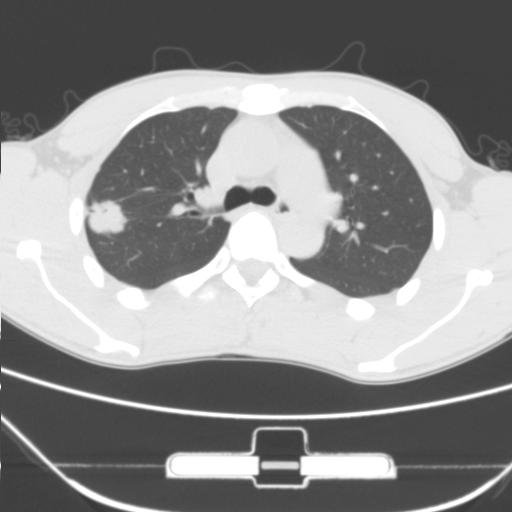

标题: CT25483:肺部病变 请指教

车祸伤者

右肺上叶后段近胸膜下结节样异常密度灶,似见分页及毛刺,考虑右肺上叶周围型肺ca,建议穿刺病理检查

缺乏病史,症状体征,但这个孤立结节具备了几乎所有的恶性征象:分叶,毛刺,空泡征,胸膜凹陷征,血管集束。